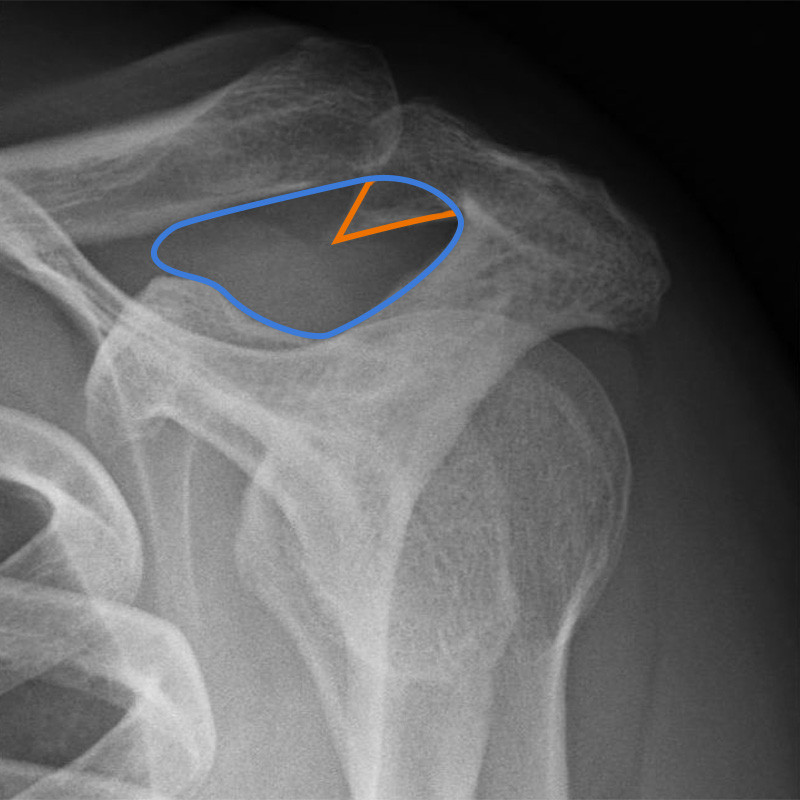

Die folgenden Röntgenbilder zeigen beispielhaft so einen Knochensporn, der die Sehne im Laufe der Jahre aufreibt:

Röntgenbilder der Schulter mit einem ausgeprägten Knochensporn: Rechts ist der Gleitraum der Rotatorenmanschette mit blau gekennzeichnet. Man kann erkennen, wie der orange eingezeichnete Sporn den Raum stark einengt.